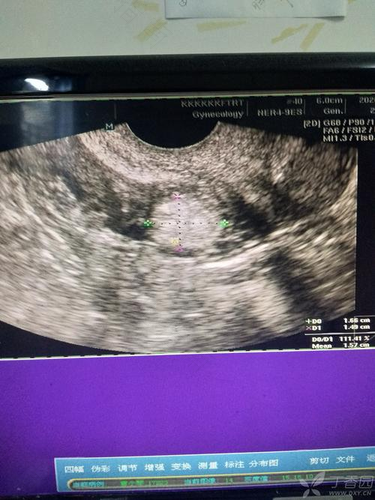

子宫是女性独有的生殖器官,而当子宫出现异常或者患有疾病时,不仅容易影响到女性健康,对其生育情况也会造成很大的影响,因此在发现子宫内有异常表现的时候,一定要及时检查并采取治疗措施。那么,宫颈处强回声怎么回事呢?

首先,当身体出现异常不适时,大多数人都会选择及时到医院进行检查,通过检查才可以对症治疗。而子宫异常也是一样。当女性身体出现异常,而通过检查发现子宫内有强回声,这种情况可能是由于女性身体患上子宫内膜息肉了,从而导致回声出现。